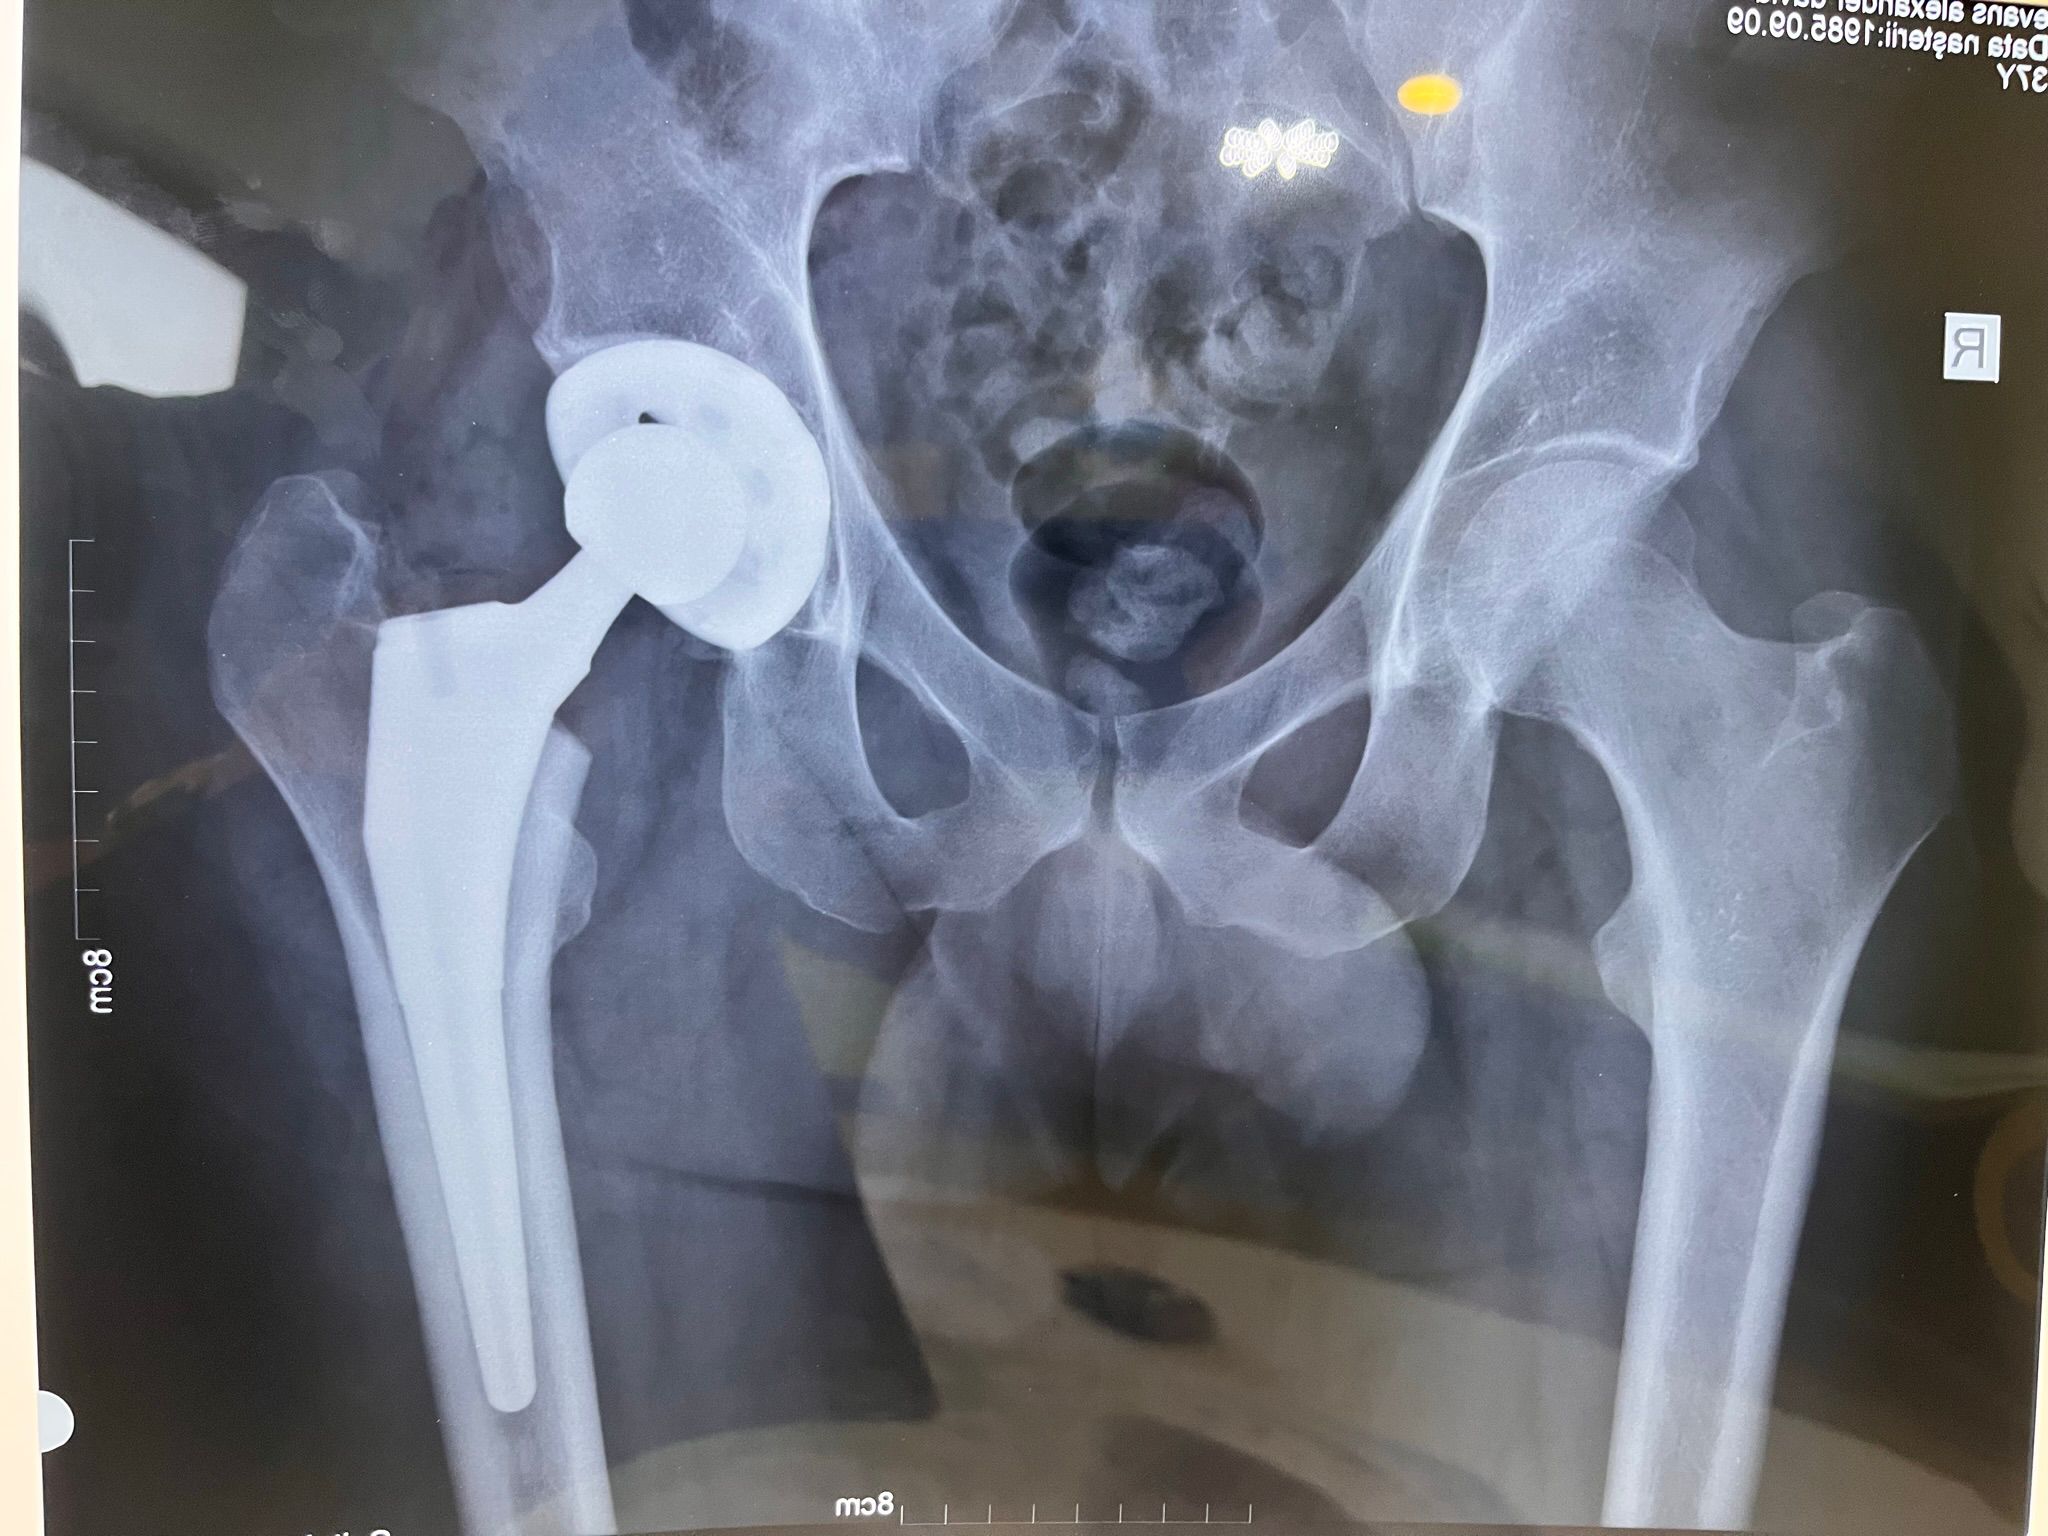

Imagini Clinice